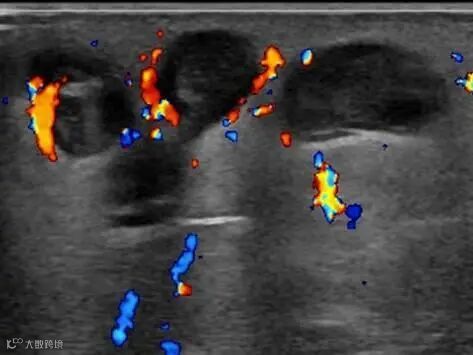

大隐静脉反流

深静脉(如股静脉、腘静脉)反流时间 > 1秒 → 功能不全

浅静脉(如大隐静脉)反流时间 > 0.5秒 → 功能不全

穿静脉反流时间 > 0.5秒 + 内径 ≥ 3.5mm → 功能不全